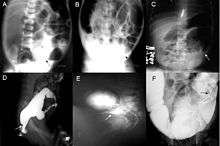

Definitive diagnosis is made by suction biopsy of the distally narrowed segment.[12] A histologic examination of the tissue would show a lack of ganglionic nerve cells. Diagnostic techniques involve anorectal manometry,[13] barium enema, and rectal biopsy. The suction rectal biopsy is considered the current international gold standard in the diagnosis of Hirschsprung's disease.[14]

Radiologic findings may also assist with diagnosis.[15] Cineanography (fluoroscopy of contrast medium passing anorectal region) assists in determining the level of the affected intestines.